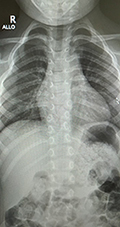

Csigolyafejlődési rendelenesség - röntgenA gyermek egyéves kora körül célszerű felkeresni az erre specializálódott szakembert, gerincsebészt. Amikor a gyermek stabilan tud állni, akkor kerül sor az első – álló helyzetű - röntgenfelvétel készítésére, amely informatív a szakemberek számára. Ennél korábban – fekvő – röntgenfelvételt nem érdemes készíttetni, hiszen terápiás jelentősége nincs, és a gyermeket lehetőség szerint óvni kell a sugárterheléstől, amit a röntgen jelent. Akkor is, ha már a magzati életben fennáll a csigolyafejlődési rendellenesség diagnózisa, csak a gyermek egyéves kora körül ajánlott a fent említett szakemberhez fordulni. Nagyon fontos, hogy a gyermek csigolyafejlődési rendellenessége miatt nem igényel speciális fejlesztést, tornát, terápiát az első hónapokban. A vizsgálat során a szakember fogja jelezni, hogy milyen gyakran szeretné látni a gyermeket, mikor esedékes a következő vizsgálat.

Csigolyafejlődési rendelenesség - röntgen Csigolyafejlődési rendelenesség - röntgen Az első vizsgálat után a gerincsebész dönt arról, milyen gyakran történjen kontrollvizsgálat. A csigolyafejlődési rendellenességgel élő gyermekeket a csontosodás befejeződésig (pubertás kor) gerincsebészi megfigyelés alatt tartják, ennek célja, hogy időben észrevegyék, ha a rendellenes csigolya miatt gerincferdülés alakul ki, amely kezelést igényel. A megfigyelés alatt tartott gyermeknek általában évente, vagy kétévente elegendő a gerincsebésznél megjelenni, és új röntgenfelvétellel ellenőrzik állapotát. A rendszeres kontrollvizsgálat lehetővé teszi, hogy – ha szükséges – időben történjen beavatkozás. A csigolyafejlődési rendellenességgel élő gyerekek sportolhatnak, mozgásban gazdag életet élhetnek, a gerincsebész útmutatásának betartásával. Gyógytornát, konzervatív kezelést nem igényelnek.